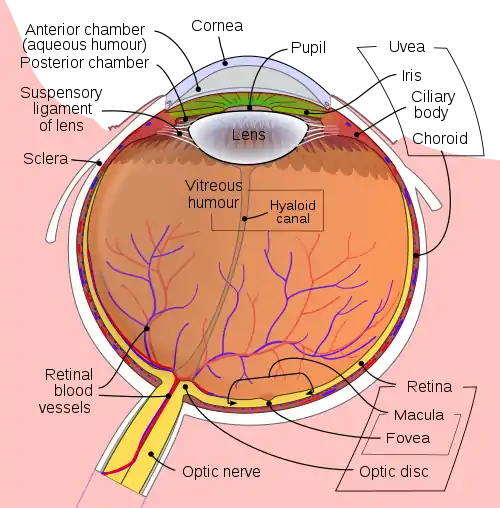

Getting inside of the eyeball - Pupil, iris and the lens

Light rays enter the eye structure through the black aperture or pupil in the front of the eye. The black appearance is due to the light being fully absorbed by the tissue inside the eye. Only through this pupil can light enter into the eye which means the amount of incoming light is effectively determined by the size of the pupil. A pigmented sphincter surrounding the pupil functions as the eye's aperture stop. It is the amount of pigment in this iris, that give rise to the various eye colours found in humans.

In addition to this layer of pigment, the iris has 2 layers of ciliary muscles. A circular muscle called the pupillary sphincter in one layer, that contracts to make the pupil smaller. The other layer has a smooth muscle called the pupillary dilator, which contracts to dilate the pupil. The combination of these muscles can thereby dilate/contract the pupil depending on the requirements or conditions of the person. The ciliary muscles are controlled by ciliary zonules, fibres that also change the shape of the lens and hold it in place.

The lens is situated immediately behind the pupil. Its shape and characteristics reveal a similar purpose to that of camera lenses, but they function in slightly different ways. The shape of the lens is adjusted by the pull of the ciliary zonules, which consequently changes the focal length. Together with the cornea, the lens can change the focus, which makes it a very important structure indeed, however only one third of the total optical power of the eye is due to the lens itself. It is also the eye's main filter. Lens fibres make up most of the material for the lense, which are long and thin cells void of most of the cell machinery to promote transparency. Together with water soluble proteins called crystallins, they increase the refractive index of the lens. The fibres also play part in the structure and shape of the lens itself.

Beamforming in the eye – Cornea and its protecting agent - Sclera

The cornea, responsible for the remaining 2/3 of the total optical power of the eye, covers the iris, pupil and lens. It focuses the rays that pass through the iris before they pass through the lens. The cornea is only 0.5mm thick and consists of 5 layers:

- Epithelium: A layer of epithelial tissue covering the surface of the cornea.

- Bowman's membrane: A thick protective layer composed of strong collagen fibres, that maintain the overall shape of the cornea.

- Stroma: A layer composed of parallel collagen fibrils. This layer makes up 90% of the cornea's thickness.

- Descemet's membrane and Endothelium: Are two layers adjusted to the anterior chamber of the eye filled with aqueous humor fluid produced by the ciliary body. This fluid moisturises the lens, cleans it and maintains the pressure in the eye ball. The chamber, positioned between cornea and iris, contains a trabecular meshwork body through which the fluid is drained out by Schlemm canal, through posterior chamber.

The surface of the cornea lies under two protective membranes, called the sclera and Tenon’s capsule. Both of these protective layers completely envelop the eyeball. The sclera is built from collagen and elastic fibres, which protect the eye from external damages, this layer also gives rise to the white of the eye. It is pierced by nerves and vessels with the largest hole reserved for the optic nerve. Moreover, it is covered by conjunctiva, which is a clear mucous membrane on the surface of the eyeball. This membrane also lines the inside of the eyelid. It works as a lubricant and, together with the lacrimal gland, it produces tears, that lubricate and protect the eye. The remaining protective layer, the eyelid, also functions to spread this lubricant around.

Where the vision reception occurs – The retina

A part of the eye, which marks the transition from non-photosensitive region to photosensitive region, is called the ora serrata. The photosensitive region is referred to as the retina, which is the sensory structure in the back of the eye. The retina consists of multiple layers presented below with millions of photoreceptors called rods and cones, which capture the light rays and convert them into electrical impulses. Transmission of these impulses is nervously initiaed by the ganglion cells and conducted through the optic nerve, the single route by which information leaves the eye.